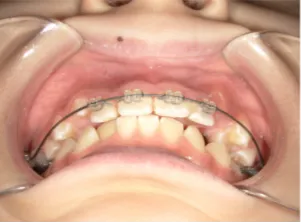

治療前①小5:生え変わり後期のため顔の成長を促進させる目的で拡大装置(アーチ形態の修正)と上顎前歯をそろえることを先行し、できるだけ非抜歯治療で進める予定を提案しました

| カウンセリング・診断結果 | 治療方法は精密検査、分析をして検討することをご理解いただき、矯正治療で抜歯をするかしないかの違いについて説明し治療を希望されたので精密検査を行いました。 精検の結果、顔立ちは下顎が後退したタイプの出っ歯(下顎後退型上顎前突)でV-shaped arch(歯列が狭い)、凸凹、八重歯になっていて、機能的にはべろのポジションが悪い低位舌があります。 口元は問題ありません。 |

| 行ったご提案・診断内容 | 生え変わりが終わってなくマルチブラケット法による咬合治療には早い時期のため、顔立ちの成長を促す目的で歯列弓(アーチ)の拡大と前歯を並べながら永久歯が生えるのを待ち、咬合治療開始時に再診断で抜歯、非抜歯を最終検討する提案をしました。 再診断時(写真②)、歯列の拡大と上顎前歯の並べ替えはされていましたが八重歯となったため抜歯、非抜歯を検討しました。 口元は特に問題がなく非抜歯で八重歯を改善するためのスペースを作ることが可能なため非抜歯治療を提案しました。 治療は、 ・拡大および上顎左右6を遠心移動させてスペースを作る 予定装置 |